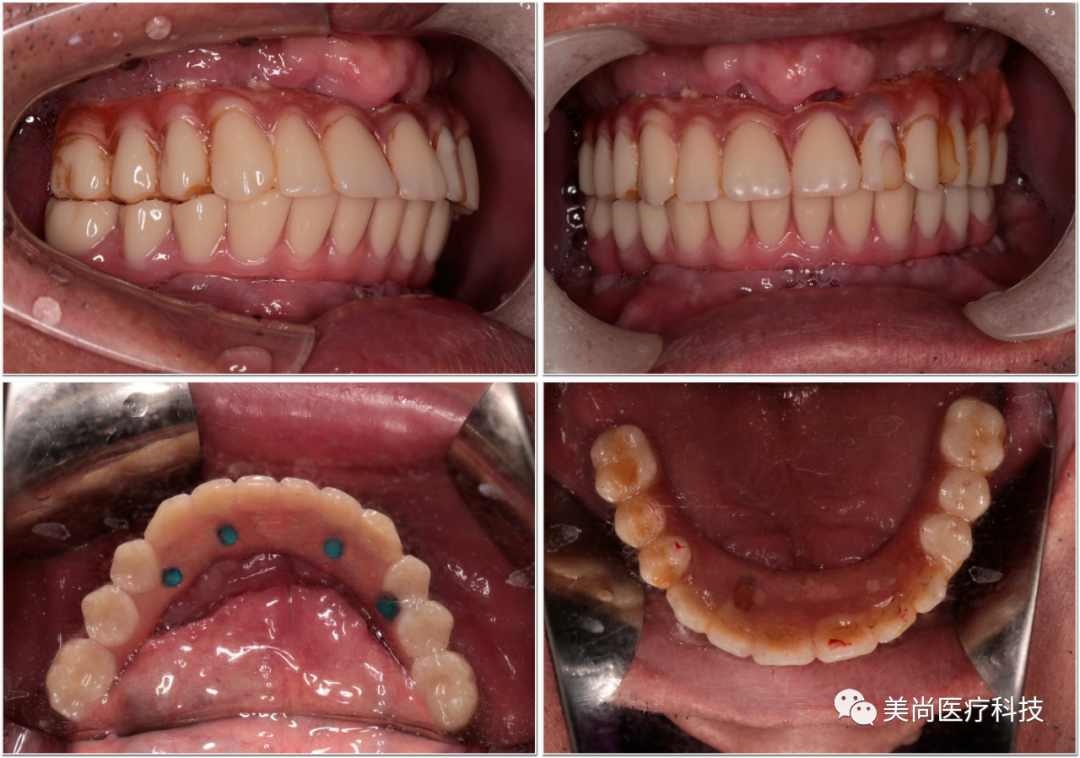

制作种植导板